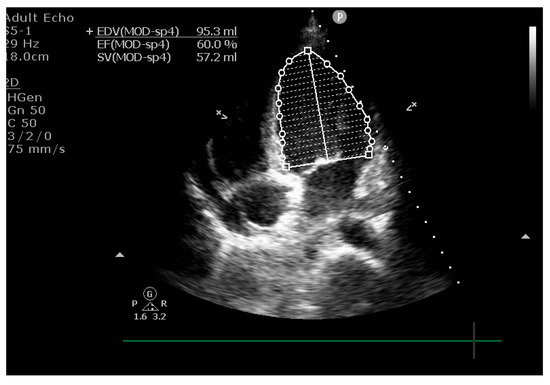

2. Case Presentation